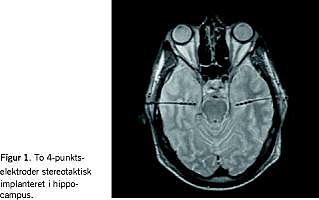

Hos en 38-årig mand med temporallapsanfald var sidelokalisationen usikker, men med stereotaktisk placerede elektroder i begge hippocampi blev der registreret velkendte anfald med tydeligt EEG-korrelat fra højre hippocampus (Figur 1 ). Som et kuriosum registreredes også epilepsisuspekt EEG-aktivitet fra dette område, men uden klinisk udtryk. Efter en selektiv hippocampektomi blev patienten anfaldsfri og uden subjektive kognitive forstyrrelser.